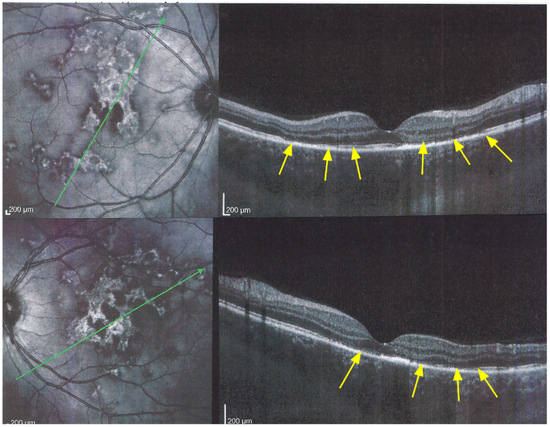

The chorioretinal findings by spectral domain optical coherence tomography (SD-OCT) depend on the degree of involvement and the stage of the disease [5,7,25]. In early-acute disease ischaemia, induced by choriocapillaris non-perfusion, causes thickening of the outer retina including the IS/OS line and beyond (Figure 8). In later stages, SD-OCT can show either simple loss of photoreceptor outer segments, thickened RPE or atrophy with loss of RPE (Figure 9).

Figure 8. APMPPE/AMIC; SD-OCT in initial-acute phase OD (top) and OS (bottom) (same patient as Figure 5, Figure 6 and Figure 7a). In this initial phase, SD-OCT shows areas of hyperreflective changes visible in the outer plexiform layer and adjacent outer nuclear layer (arrows) but no loss of photoreceptor outer segments (see Figure 5).